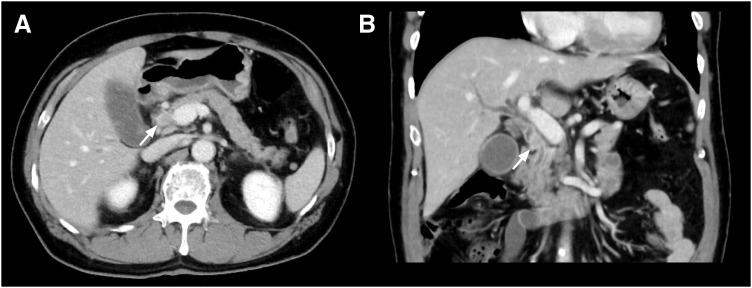

A 67-year-old man was referred to our hospital for evaluation of jaundice. Contrast-enhanced computed tomography revealed an enhanced tumor on the common bile duct. Endoscopic retrograde cholangiography showed bile duct stenosis due to a nodular tumor of the common bile duct. We performed subtotal stomach-preserving pancreaticoduodenectomy under diagnosing distal cholangiocarcinoma. The patient was discharged on the 23rd postoperative day. Macroscopic findings of the resected specimen showed a 27-mm nodular-infiltrating tumor at the middle bile duct and a 3-mm nodular tumor at the lower bile duct. The distance between the tumors was 10 mm. Pathological examination revealed that the larger tumor was primarily composed of poorly differentiated adenocarcinoma, with a moderately differentiated component at the periphery of the tumor. The smaller tumor was entirely composed of poorly differentiated adenocarcinoma, which was similar to the poorly differentiated component of the larger tumor. Additionally, microscopic lymphovascular infiltration was observed in the vicinity of both tumors. These two lesions were separated by nontumoral biliary epithelia without atypia. The results of immunohistochemical staining using CK7/20, MUC1/2, and p53 antibodies substantiated the homology of these tumors. These results suggested that the smaller tumor was synchronous intramural bile duct metastasis of distal cholangiocarcinoma rather than independent multiple lesions.

一名67岁男性因黄疸来我院就诊。增强计算机断层扫描显示胆总管上有一个强化肿瘤。内镜逆行胆管造影显示胆总管的结节状肿瘤导致胆管狭窄。我们在诊断为远端胆管癌的情况下进行了保留胃的胰十二指肠次全切除术。患者术后第23天出院。切除标本的宏观检查显示,在胆总管中部有一个27毫米的结节浸润性肿瘤,在胆总管下部有一个3毫米的结节状肿瘤。两个肿瘤之间的距离为10毫米。病理检查显示,较大的肿瘤主要由低分化腺癌组成,肿瘤周边有中分化成分。较小的肿瘤完全由低分化腺癌组成,与较大肿瘤的低分化成分相似。此外,在两个肿瘤附近均观察到微小淋巴管浸润。这两个病变被无异型性的非肿瘤性胆管上皮分隔开。使用CK7/20、MUC1/2和p53抗体进行免疫组化染色的结果证实了这些肿瘤的同源性。这些结果表明,较小的肿瘤是远端胆管癌的同步壁内胆管转移,而不是独立的多发病变。